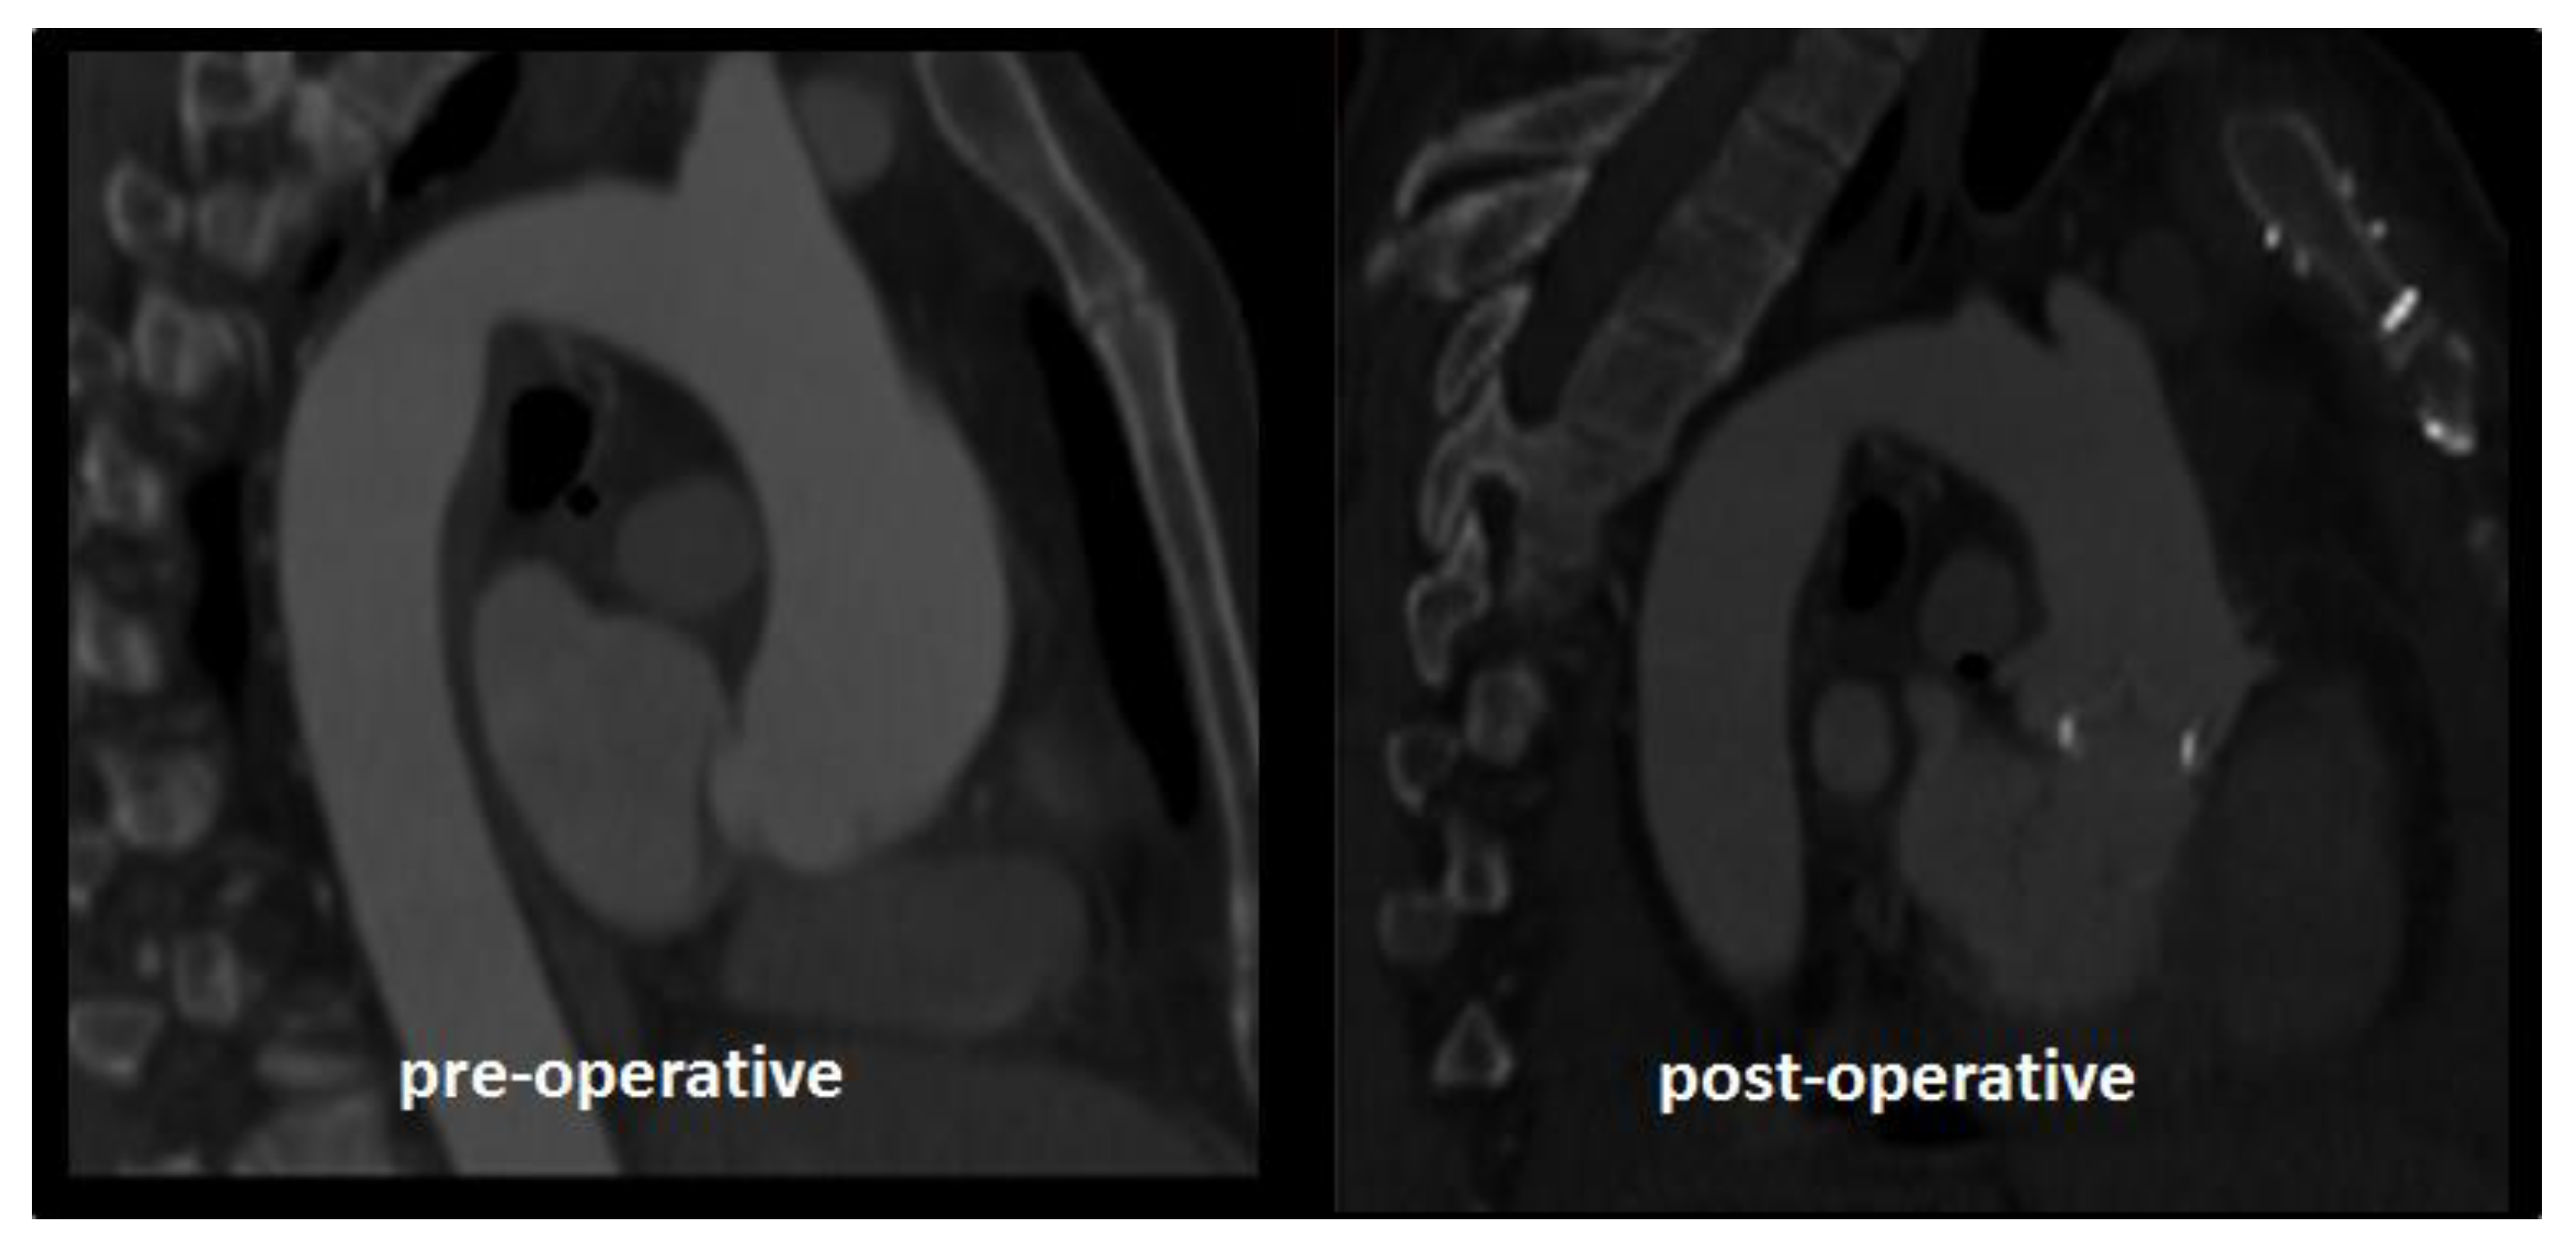

2.1. Case Study